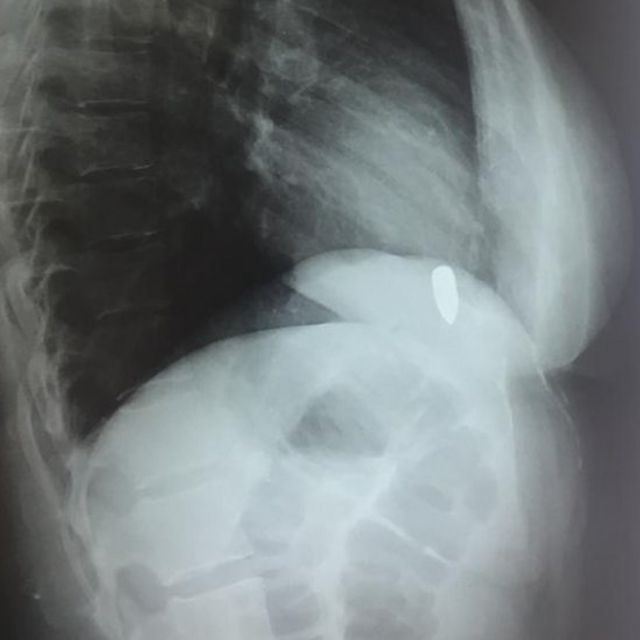

எக்ஸ் ரேவில் தெரியும் துப்பாக்கி தோட்டா

"எக்ஸ்-ரே எடுத்துப் பார்த்ததில், இதயத் துடிப்போடு தோட்டாவும் மேலேயும் கீழேயும் நகர்ந்தது தெரிந்தது. ஆறு மாதமாக இவர் இதை அனுபவித்து வந்ததால் எனக்கு அந்தப் பெண் குறித்து அதிக கவலை ஏற்பட்டது."